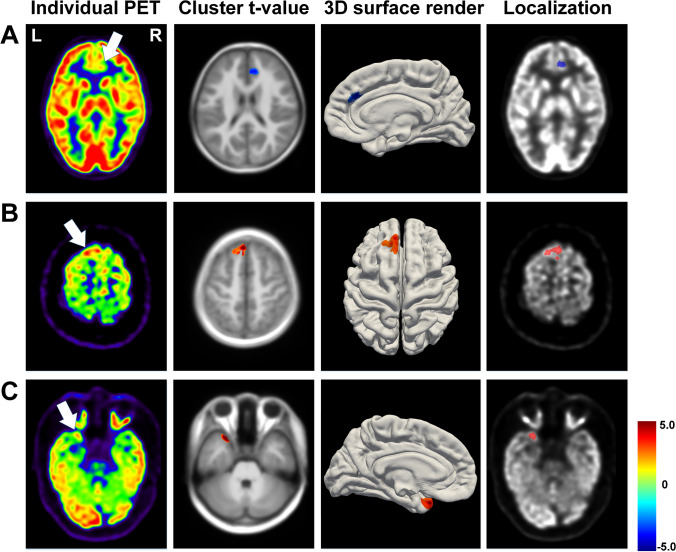

Fig. 5.

Localization results of patients whose foci were missed by routine visual assessment. A A 9-year-old boy: right frontal lobe hypo-metabolism, peak-t = − 4.04, cluster size = 963; B 18-year-old boy: left frontal lobe hyper-metabolism, peak-t = 7.37, cluster size = 1387; C 15-year-old boy: left temporal lobe hyper-metabolism, peak-t = 8.16, cluster size = 452 (P < 0.01, cluster size > 100)

Routine visual assessment missed epileptogenic foci in 8 patients with temporal lobe epilepsy (TLE) and 37 with extra-TLE. Twelve of these patients showed hyper-metabolism, and six were visually diagnosed as contralateral hypo-metabolism. The PAPT-based analysis identified 82.2% (8 TLE and 29 extra-TLE) of these patients, while the linear and adult template-based analyses could only identify 71.1% and 64.5% of these patients, respectively. In total, 19 patients showed interictal hyper-metabolism, and all could be detected by PAPT-based analysis. Figure 5 illustrates localization results of 3 representative patients (A–B: visually negative patients with hypo- and hyper-metabolism, respectively; C: a patient who was visually diagnosed as contralateral hypo-metabolism). Furthermore, visual assessment could detect foci in 7 of 14 patients with negative findings in PAPT-based analysis.